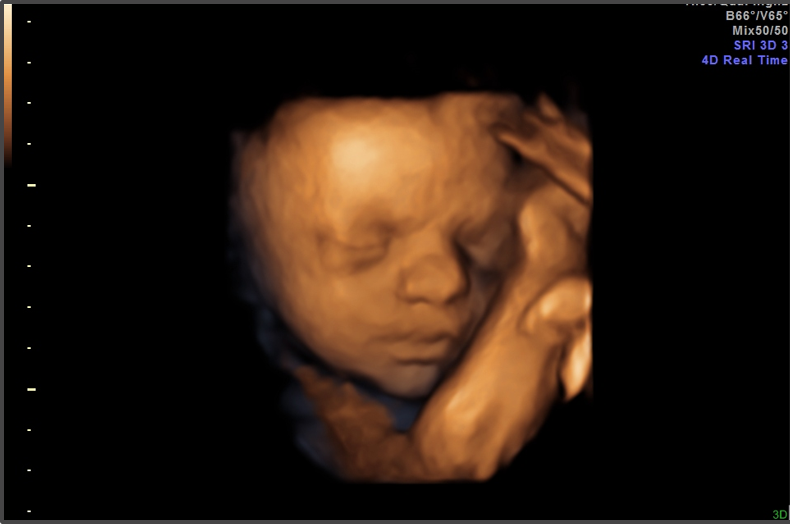

When the Supreme Court decided Dobbs v. Jackson, Americans were told a simple story: abortion policy would return to the states. Whatever one’s moral view, the constitutional logic was clear. States would once again be allowed to regulate abortion according to their own laws, voters, and medical standards.

That promise now looks increasingly hollow.